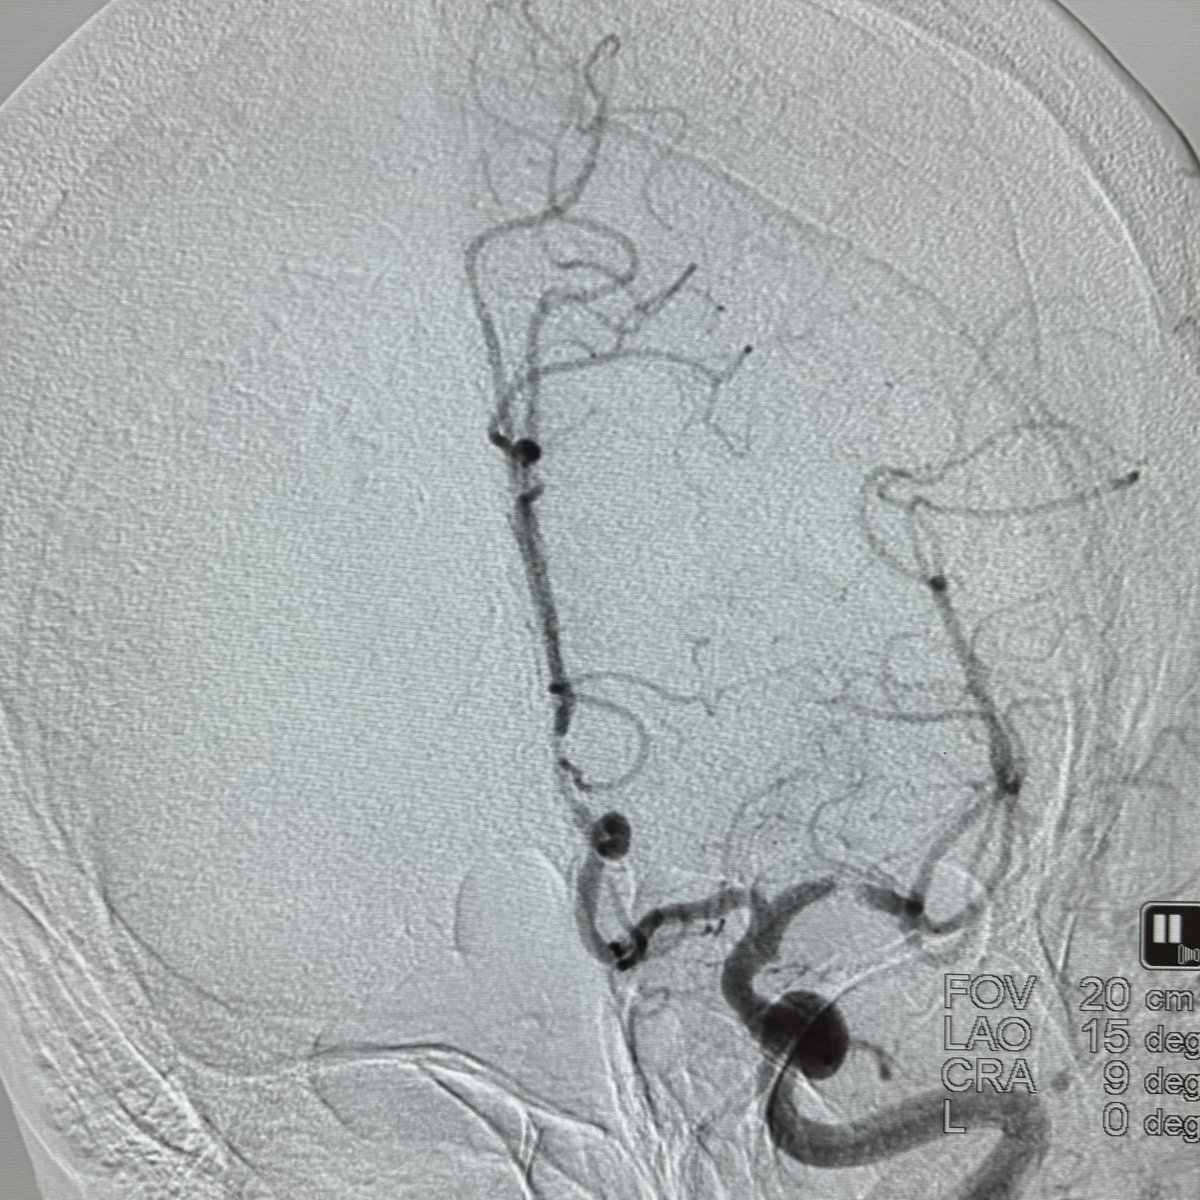

This 🧔♂️ presents with a subarachnoid haemorrhage in the left suprasellar cistern

DSA shows an infundibulum/ aneurysm of the left PCom. To coil or not was a conundrum. Every expert has a different take

The size is 3.4 mm x 2.6 and it is located in the region of the bleed.

What would you do?